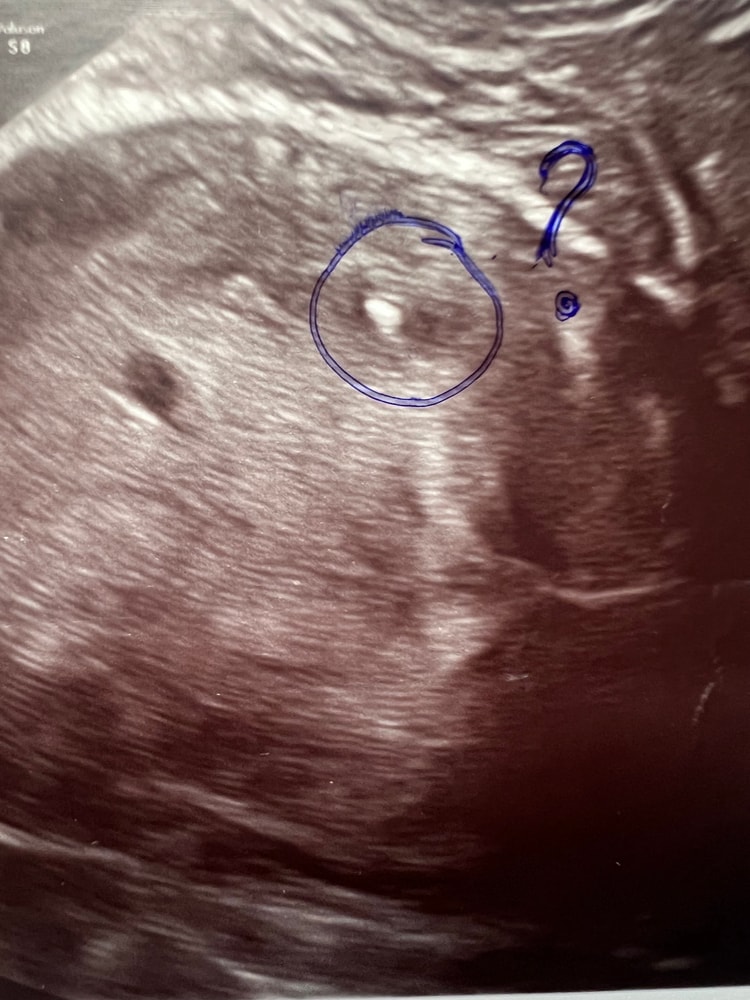

Двое? Посмотрите узи кто может, нам 6 недель

Два 100%)) Третий под вопросом))

07.02.2014

У меня так было. На 6й неделе второй под вопросом, думали может гематома. А на 7й уже слушали два сердечка:-):-):-):-)

А что между ними? Я вижу три)))

06.02.2014

Вот и я тоже вижу три, но Г третий даже не прокомментировал. Во время просмотра этого третьего было не видно он как то проявился в момент снимка )))